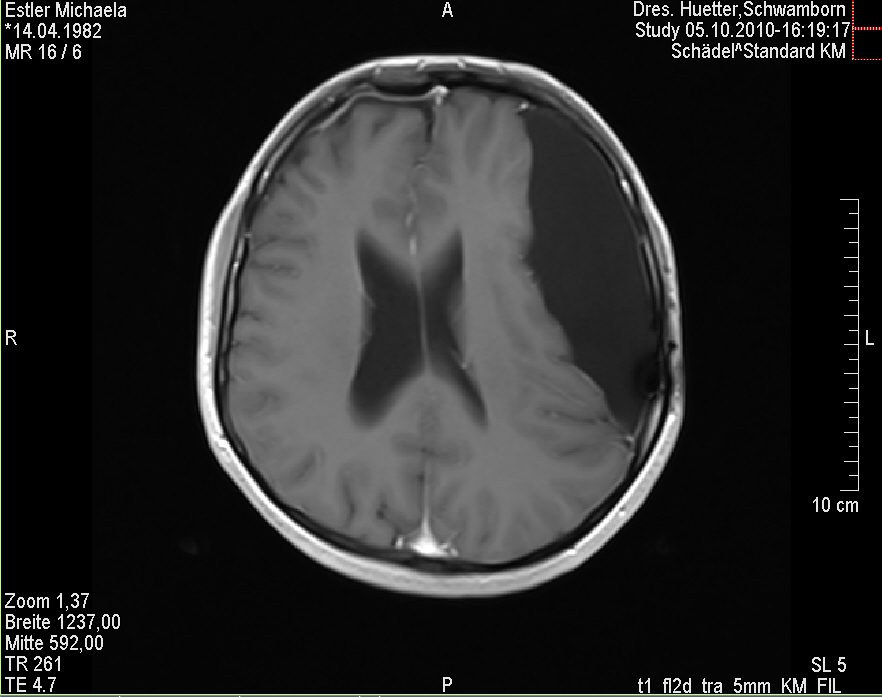

Ich stell euch hier noch eine kleine Galerie rein mit den neuesten Bildern. Ich denke es ist unübersehbar, dass das Ding gewachsen ist, außerdem mir meine komplette Hirnmittelline verschiebt und immer mehr Rücklagerung bekommt und Richtung Hirnsteuerungszentrum drückt. Meine häufiger auftretenden Stürze und Koordinationsprobleme werden also in naher Zukunft sicherlich nicht weniger werden und mein Doc und ich werden uns wohl auch zeitnah über eine weitere Klinik und eine mögliche weitere OP unterhalten müssen.